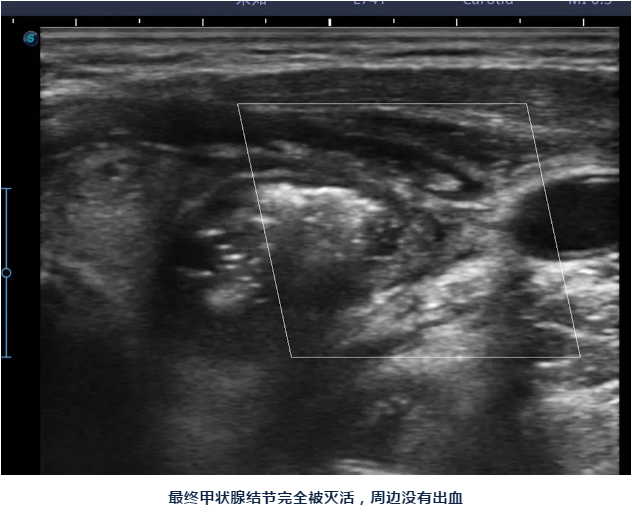

陈主任说:甲状腺结节消融做完后脖子上只有一个针眼,术后也不影响活动、进食,同时手术是在超声引导下进行,只消融结节,能尽最大限度保护正常甲状腺组织,也可以清楚避开血管、气管、食管、神经等周边组织器官,术后出现声音嘶哑、出血、甲减的几率要小很多。

手术在局麻下进行,历时一个多小时就结束了,术后王女士马上就可以下地活动,一个小时后就可以进食,手术的小针眼第二天就基本痊愈,王女士的脖子也看不出肿大了,感觉美观多了。

陈主任告诉王女士,甲状腺结节消融后第二天就可以出院了,之后结节会逐渐吸收、缩小,一般一个月后体积能缩小50%左右,一年后体积能缩小90%以上,小一点的结节可以完全消失,以后按时到医院复查即可。